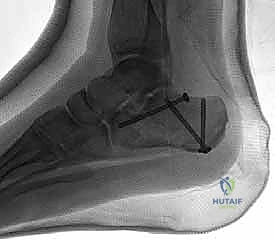

- التصوير بالأشعة السينية (X-rays): لأخذ فكرة أولية عن الكسر (زوايا بوهلر وجيسان - Bohler’s and Gissane’s angles).

- الأشعة المقطعية (CT Scan): وهي الخطوة الأهم والأكثر حيوية. توفر الأشعة المقطعية صوراً ثلاثية الأبعاد وتقاطعاً دقيقاً للكسر، مما يسمح بتصنيف الكسر (نظام ساندرز - Sanders Classification) وتحديد عدد الشظايا العظمية ومدى انزياحها داخل المفصل. بناءً على هذه الأشعة، يضع الدكتور هطيف خطته الجراحية الدقيقة.

5. التثبيت النهائي باستخدام الشرائح والمسامير (Plating)

يتم وضع شريحة تيتانيوم (Titanium Plate) مصممة خصيصاً لتطابق الشكل التشريحي لعظم الكعب. يتم تثبيت هذه الشريحة بمسامير قوية لتوفير ثبات ميكانيكي صلب يسمح بالالتئام السليم ويمنع انهيار العظم مرة أخرى. في بعض الحالات التي يوجد فيها فراغ عظمي كبير، قد يستخدم الدكتور هطيف طعوماً عظمية (Bone Grafts) لملء الفراغ.

صور إضافية من داخل غرفة العمليات توضح دقة الإجراء

توضح الصور التالية مدى تعقيد الجراحة والدقة التي يتطلبها تثبيت عظم الكعب، والتي يعكسها التميز الجراحي للأستاذ الدكتور محمد هطيف: